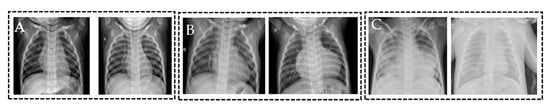

3.1. Dataset

3.2. Preprocessing